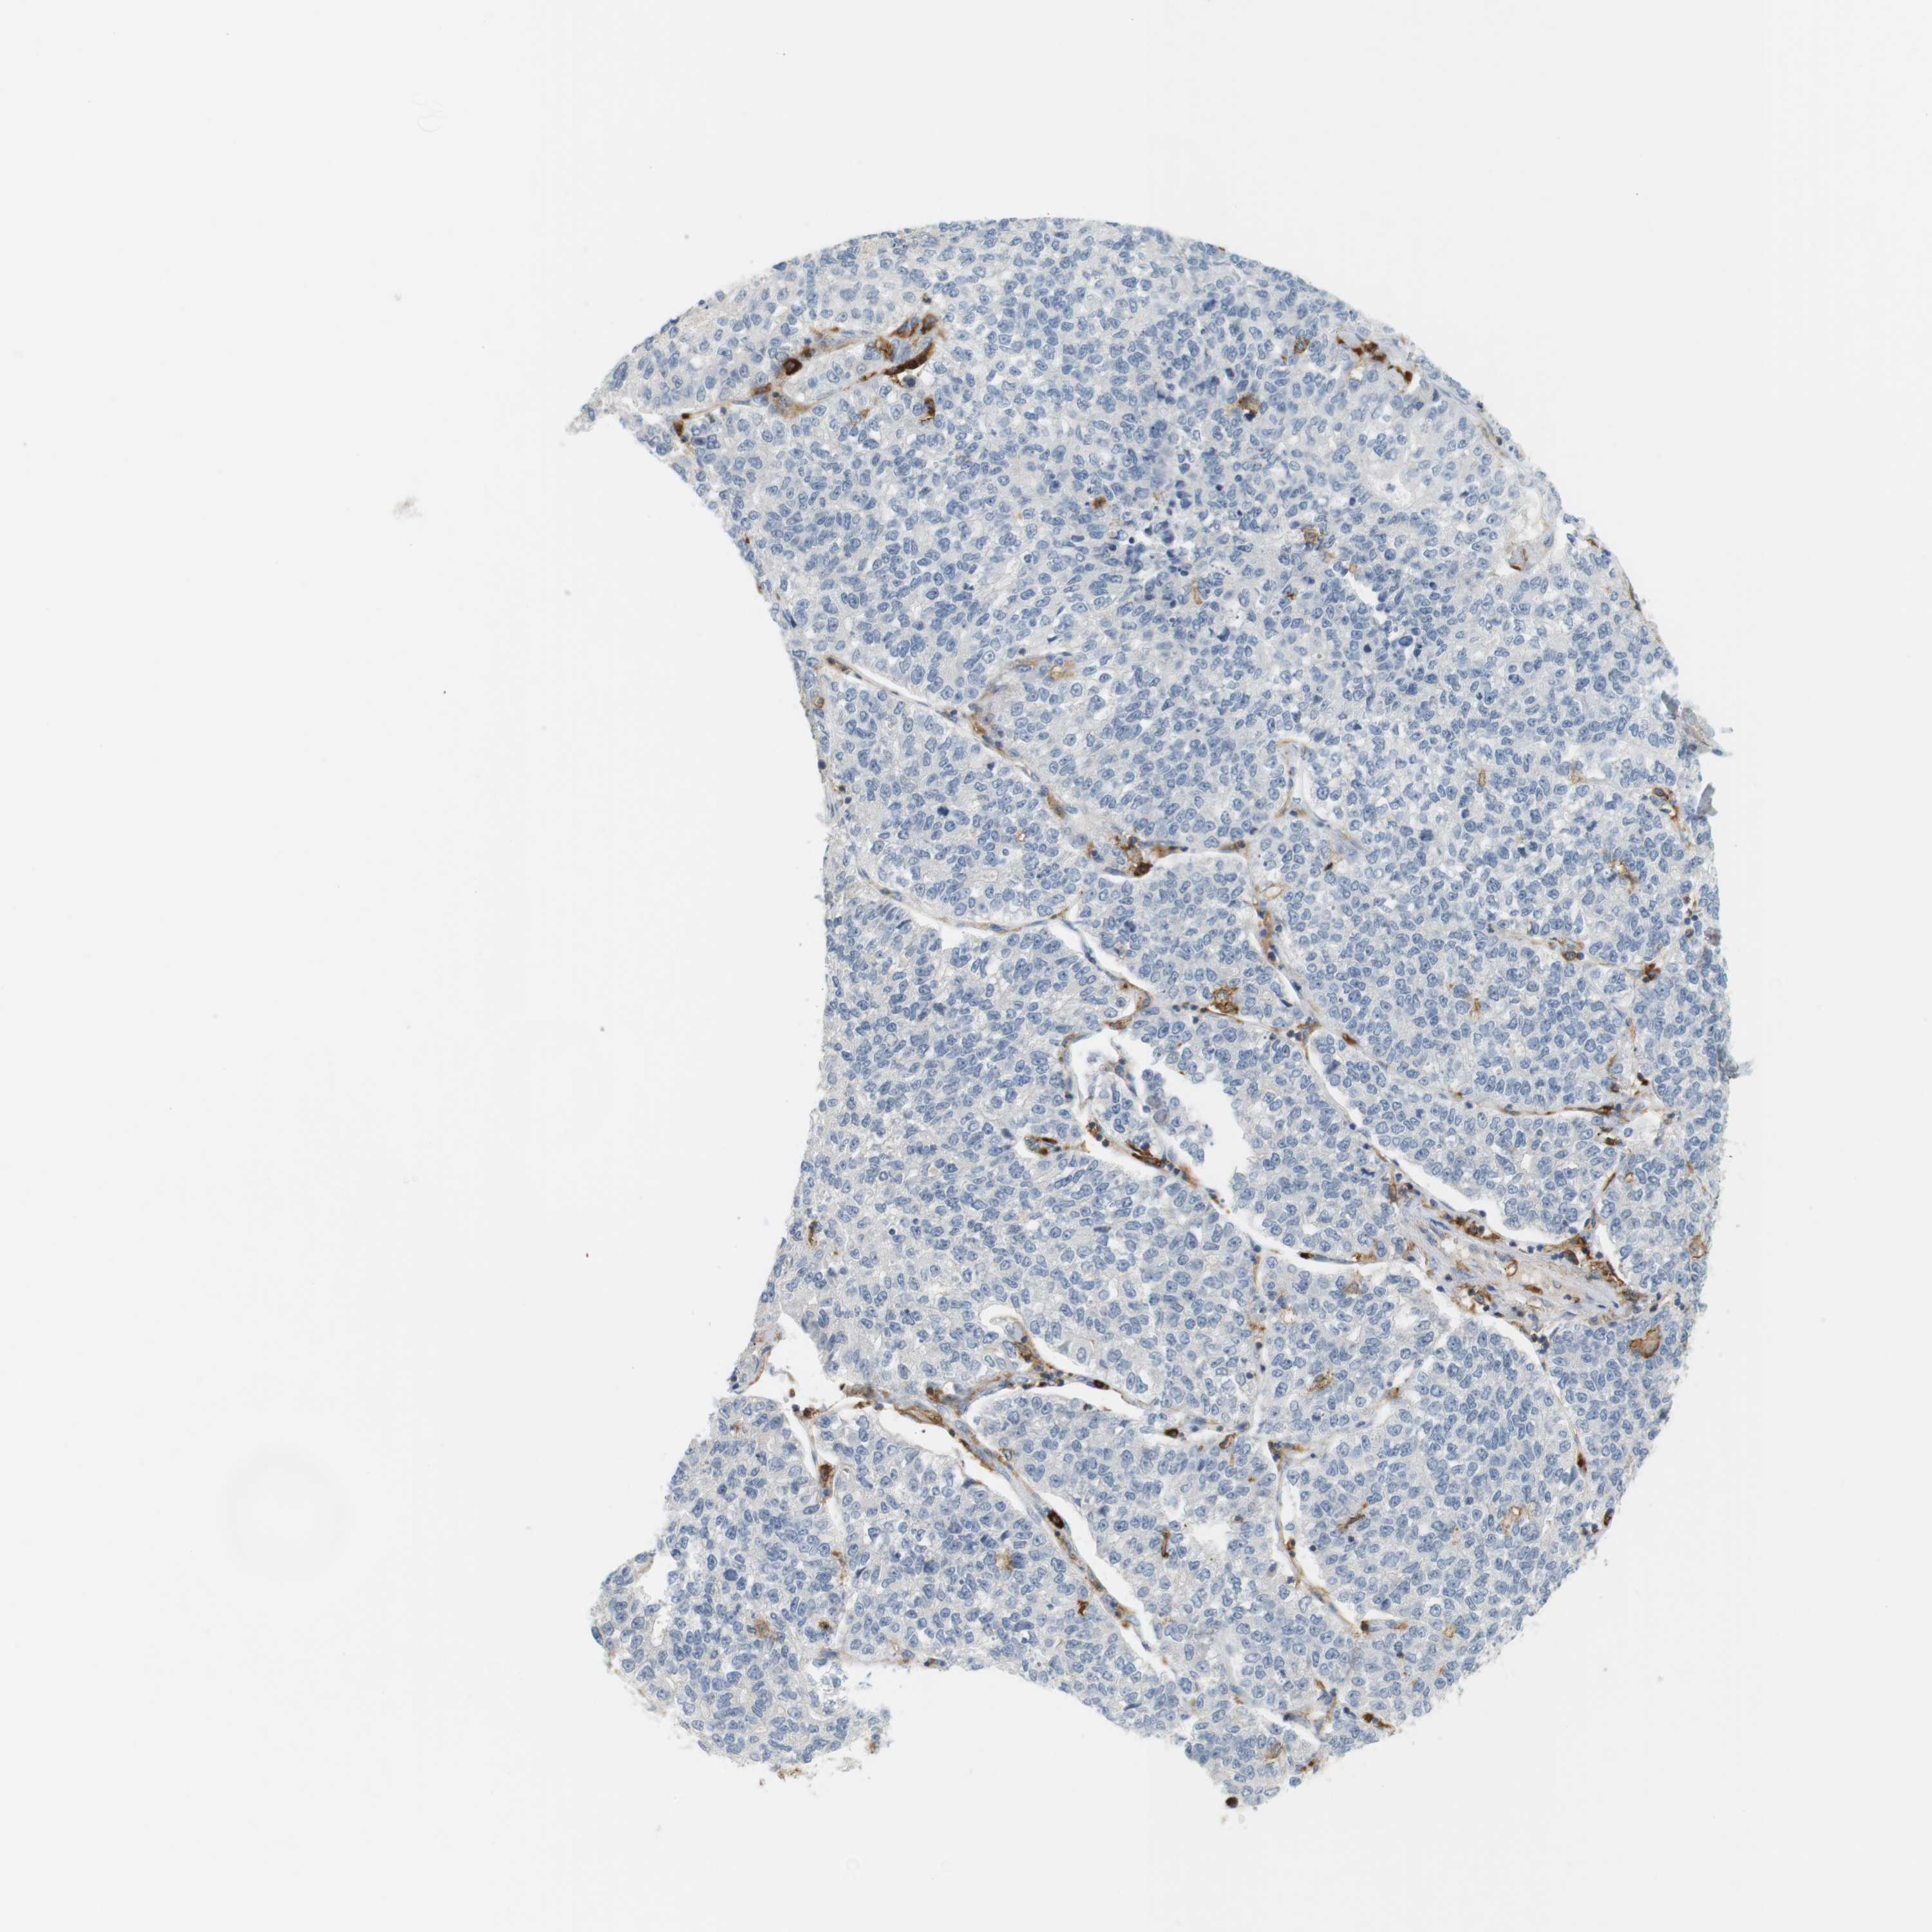

CANCER LUNG CANCER Show tissue menu

LUAD TCGA LUAD VALIDATION LUSC TCGA LUSC VALIDATION PROTEIN LUAD CPTAC PROTEIN LUSC CPTAC PROTEIN EXPRESSION